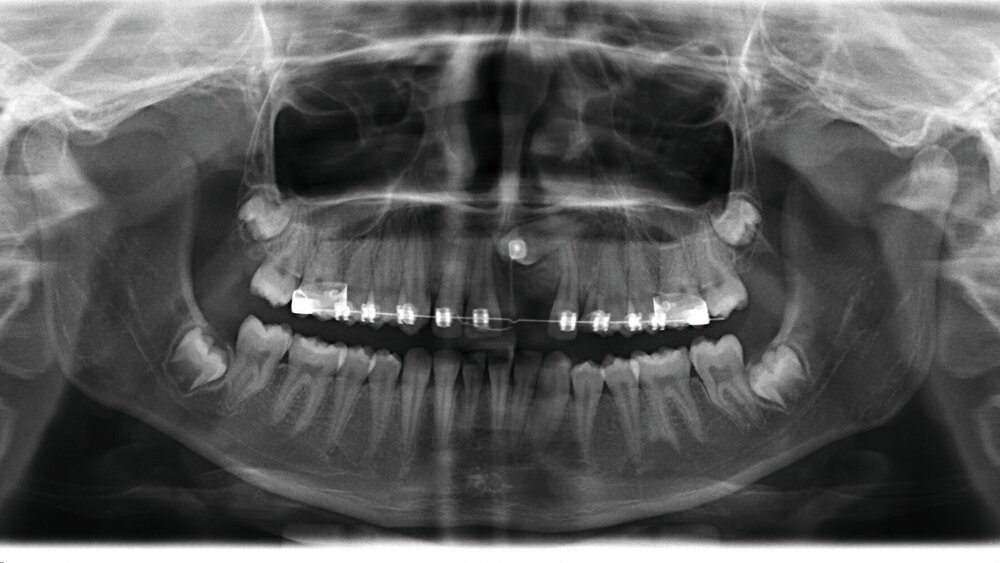

Die kieferorthopädische Behandlung der Patientin wurde im Mai 2018 (alio loco) begonnen. Zu diesem Zeitpunkt war die Patientin zehn Jahre alt. Bei der Erstellung des Behandlungsplans wurde der Fall initial als fehlender linker Eckzahn im Oberkiefer diagnostiziert. Vor der Extraktion des Schneidezahns wurde eine CT-Aufnahme durch den Erstbehandler angewiesen. Die Bildgebung ergab, dass der obere mittlere Schneidezahn sowie der Eckzahn auf der linken Seite betroffen waren (Abbildung 1). Die Patientin wurde daraufhin vom Erstbehandler zur Extraktion des impaktierten Zahnes 21 überwiesen.